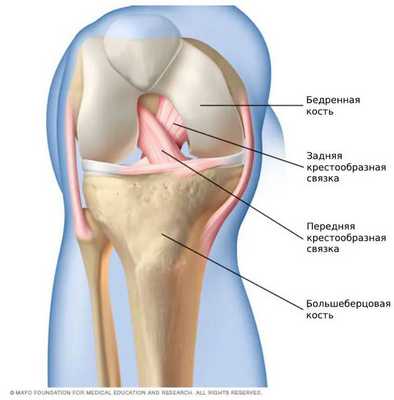

Патогенез разрыва передней крестообразной связки

Передняя крестообразная связка состоит из спирально расположенных коллагеновых волокон, которые обеспечивают её прочность и растяжимость [7] [10] . Своим верхним концом ПКС прикрепляется к бедренной кости, а нижним — к большеберцовой. На середине хода ПКС пересекается с задней крестообразной связкой. И з-за характерного перекрёста данные связки и получили своё название [8] [9] .

![Передняя и задняя крестообразные связки [15]](/pimg3/priznaki-radialnogo-razriva-4A6CCBC.jpg)

Передняя крестообразная связка состоит из трёх пучков:

- Передневнутренний — самый длинный, расположен поверхностно и наиболее подвержен травмам. Как правило, при частичных повреждениях связки разрывается именно он.

- Задненаружный — лежит глубже предыдущего, наименее подвержен разрывам.

- Промежуточный.

Основная функция ПКС — удерживать голени от смещения. Чаще всего разрывы связки вызваны кручением на опорной ноге, когда бедро и корпус вращаются, а голень со стопой остаются фиксированными. Повреждение ПКС приводит к нестабильности в коленном суставе, т. е. дискомфорту от смещения голени относительно бедра.